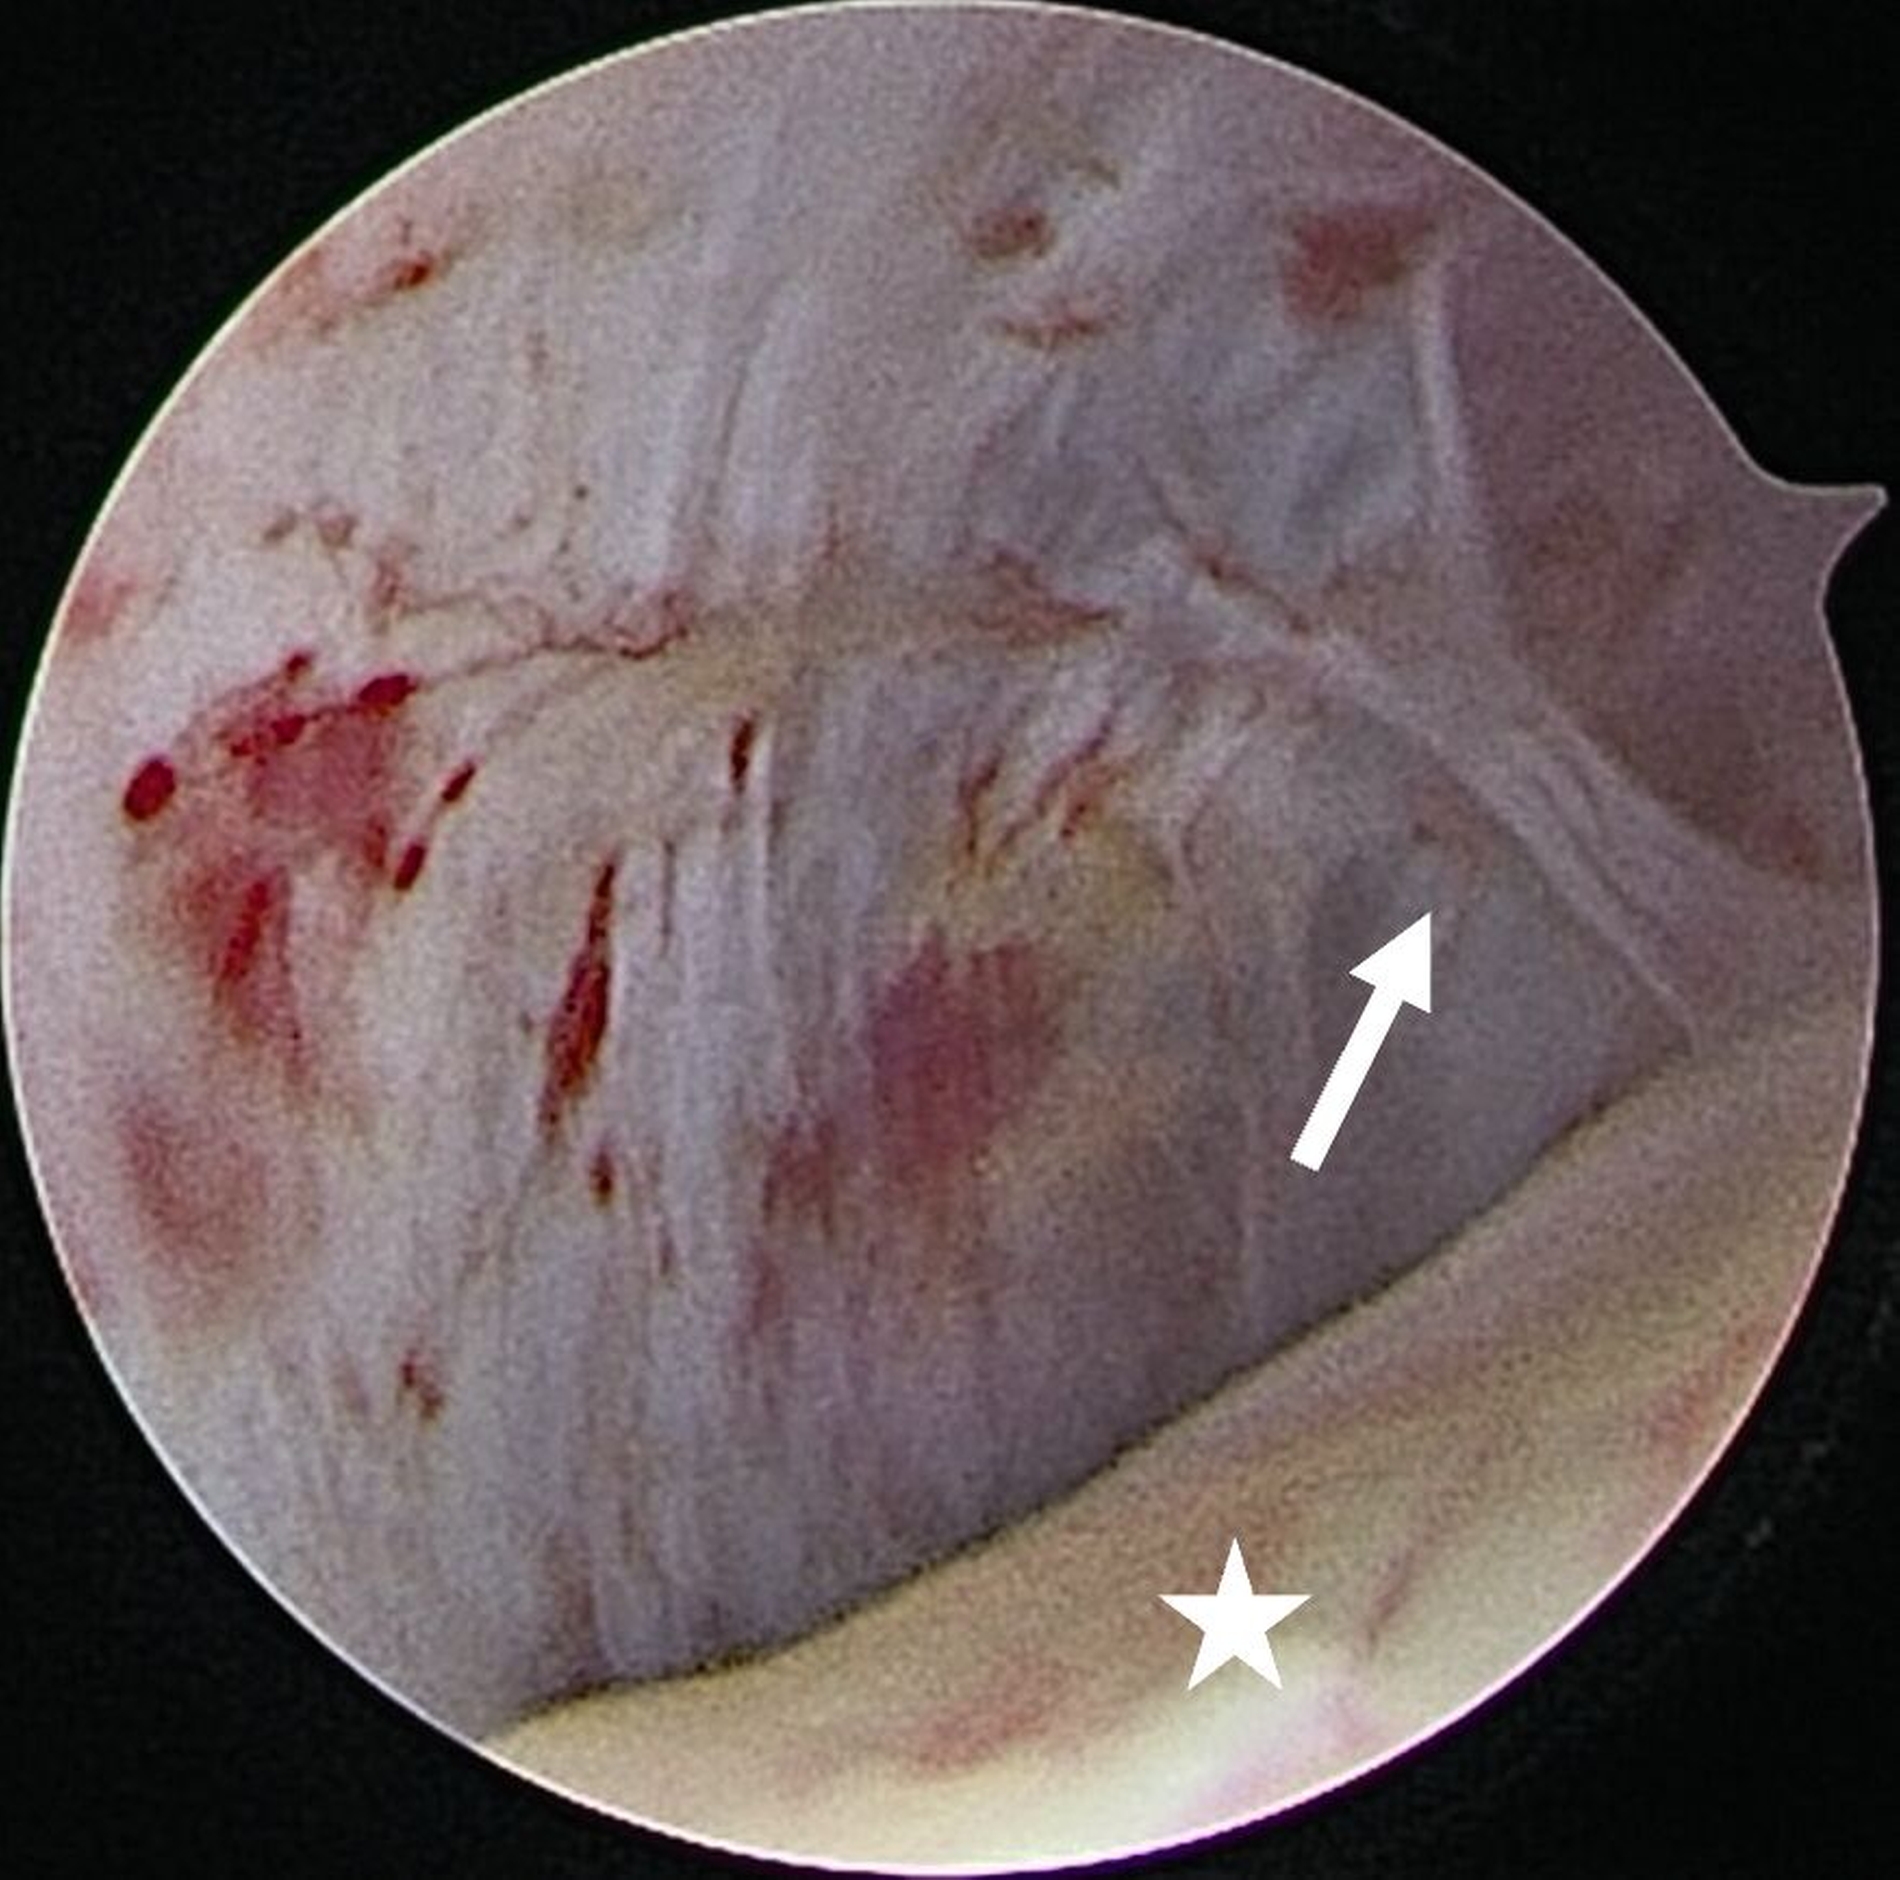

Eine Entzündung im Bereich der Gelenkkapsel (Synovitis) stellt eine häufige Ursache für arthrogen bedingte Beschwerden dar [Mercuri et al., 2025]. Neben der Darstellung des Gelenks und der Behandlung von Pathologien beruht ein positiver Effekt der Arthroskopie auf der Lavage des Gelenks. Dadurch können zum Beispiel proinflammatorische Mediatoren entfernt und intraartikuläre Adhäsionen gelöst werden [Soni, 2019]. Abbildung 2 zeigt die intraoperativen Befunde von zwei Patienten. Es wird jeweils der Übergang zwischen dem hinteren Aufhängungsband und der pars posterior des Discus articularis dargestellt.